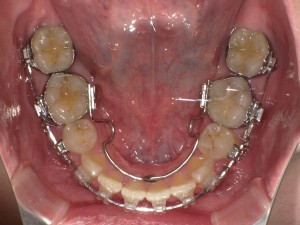

【After:H29.6.6】

まず装置に関してですが、上下とも裏側についていた装置が取れました!

下は前歯の根元あたりにかぶっていてとても磨きづらかったのですが、取ってからすっきりおもいっきり磨けるようになりました!

ここはよく歯石がたまりやすいところなので引き続き意識して磨いていきます\(^o^)/

上は食べ物を飲み込むときにひっかかる奥側の装置がまだ残っているので細いものは不便ですが、

舌が当たる感覚が少なくなったので快適です!

上の歯の前から3番目と4番目の歯の間の隙間も少なくなってきました!